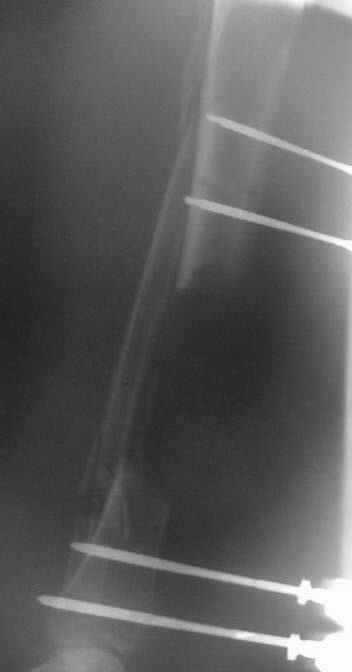

This Patient have to be treated by using Ilizarov bifocal bone transport, aproximatly as showen here.

Levels and direction of osteo/corticotomy lines can be discussed - but more detailed images are necessary (loks like initial ones were taken with a mobile phone).